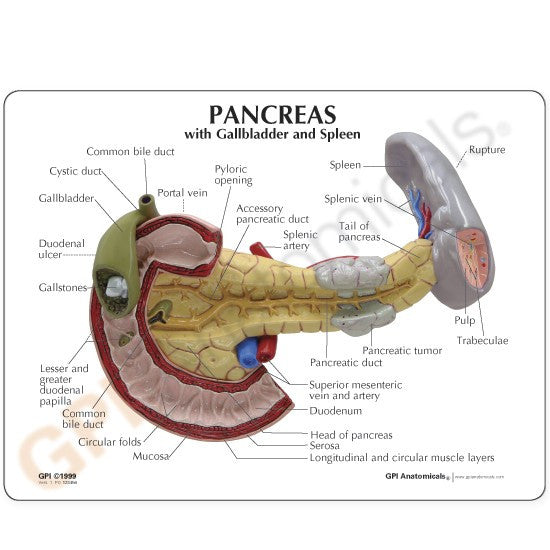

Enhance medical education with our collection of digestive system anatomical models including the stomach, liver, gallbladder, pancreas & colon models. Discover the anatomy of healthy organs as well as common gastrointestinal diseases such as stomach ulcers, gallstones and liver cirrhosis. Our digestive system anatomy posters are ideal for study and patient education.

At AnatomyStuff we stock a diverse range of digestive system anatomical models to suit your training needs. From budget models and affordable medical education posters to highly advanced 3D printed bowel models, you can transform medical training and patient education. As well as our own exclusive collection, we are proud resellers of 3B Scientific, Anatomy Lab, Denoyer-Geppert Science Company, ESP Models, Erler Zimmer and GPI Anatomicals. Explore our exclusive collection of digestive system anatomy charts, posters, fine art prints and digital anatomy study guides. Discover the anatomy of key organs like the liver, stomach, pancreas and bowel as well as the pathophysiology of common conditions like peptic ulcer disease, coeliac disease, IBD and much more. We have anatomy posters suitable for school children all the way up to medical degree level. From a liver anatomy poster to a digital study guide all about common GI disorders, find exactly what you need right here to enhance medical training and patient education.